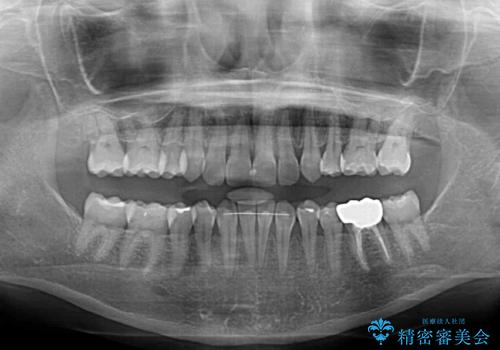

マウスピースでの抜歯矯正特有の抜歯スペースに向かって奥歯が傾斜する動きが顕著に表れ、ディープバイトは改善されませんでした。

前歯のみが強く接触し、奥歯で咬めない期間も続いたため、ワイヤー装置などを補助的に使用し、何とか終了させることができました。